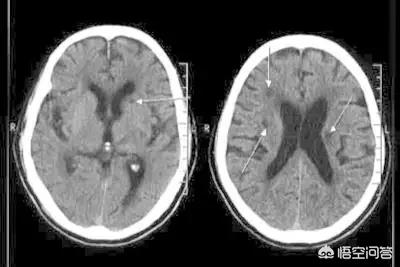

なぜか?脳血管障害には主に脳出血と脳梗塞がありますが、臨床的な予後は発症部位と病変の大きさに密接に関係しています。 発症部位が重要で病変の範囲が大きいと予後は非常に悪くなり、その逆も同じ理由です。最も予後が悪いのは大きな脳梗塞と大きな脳出血で、基本的には死に至ります。

脳梗塞。

1、早期脳梗塞:脳梗塞発症から6時間以内が血栓溶解療法に最も適した時間帯である。適時に血管を開き、脳組織の代謝を改善する。合併症や後遺症を防ぐことができる。大動脈血栓症に対しては、血管血栓の摘出が可能である。6時間以内に最高の効果が得られ、遅くとも24時間を超えることはない。

2、後期脳梗塞:血栓溶解と血栓除去の条件を失い、慢性期になった患者。リハビリテーションが主な治療で、脳循環改善薬や栄養神経改善薬で補う。しかし、糖尿病、高血圧、高脂血症などの基礎疾患の治療にはもっと注意を払うべきである。

脳出血。

1、脳出血の急性期:出血量が30ml以下、または血腫の直径が3cm以下の場合は、脱水と頭蓋内圧を下げる薬物で血腫を治療する。出血量が30ml以上の場合は、手術で血腫を除去する。